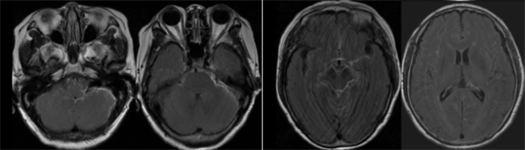

接诊的神经内一科黄娜雁医生仔细检查发现,患者的颈部明显僵硬(脑膜刺激征阳性),敏锐地意识到这很可能与脑膜病变有关。由于脑膜病变往往需要增强磁共振才能看清,黄娜雁立即为她安排了检查,结果果然显示广泛的脑膜强化,符合脑膜炎特征。

(2)影像学检查:CT检查:可发现脑部病变;磁共振(MRI):更清晰,能显示脑膜增厚、脑积水、结核瘤等特征性变化。